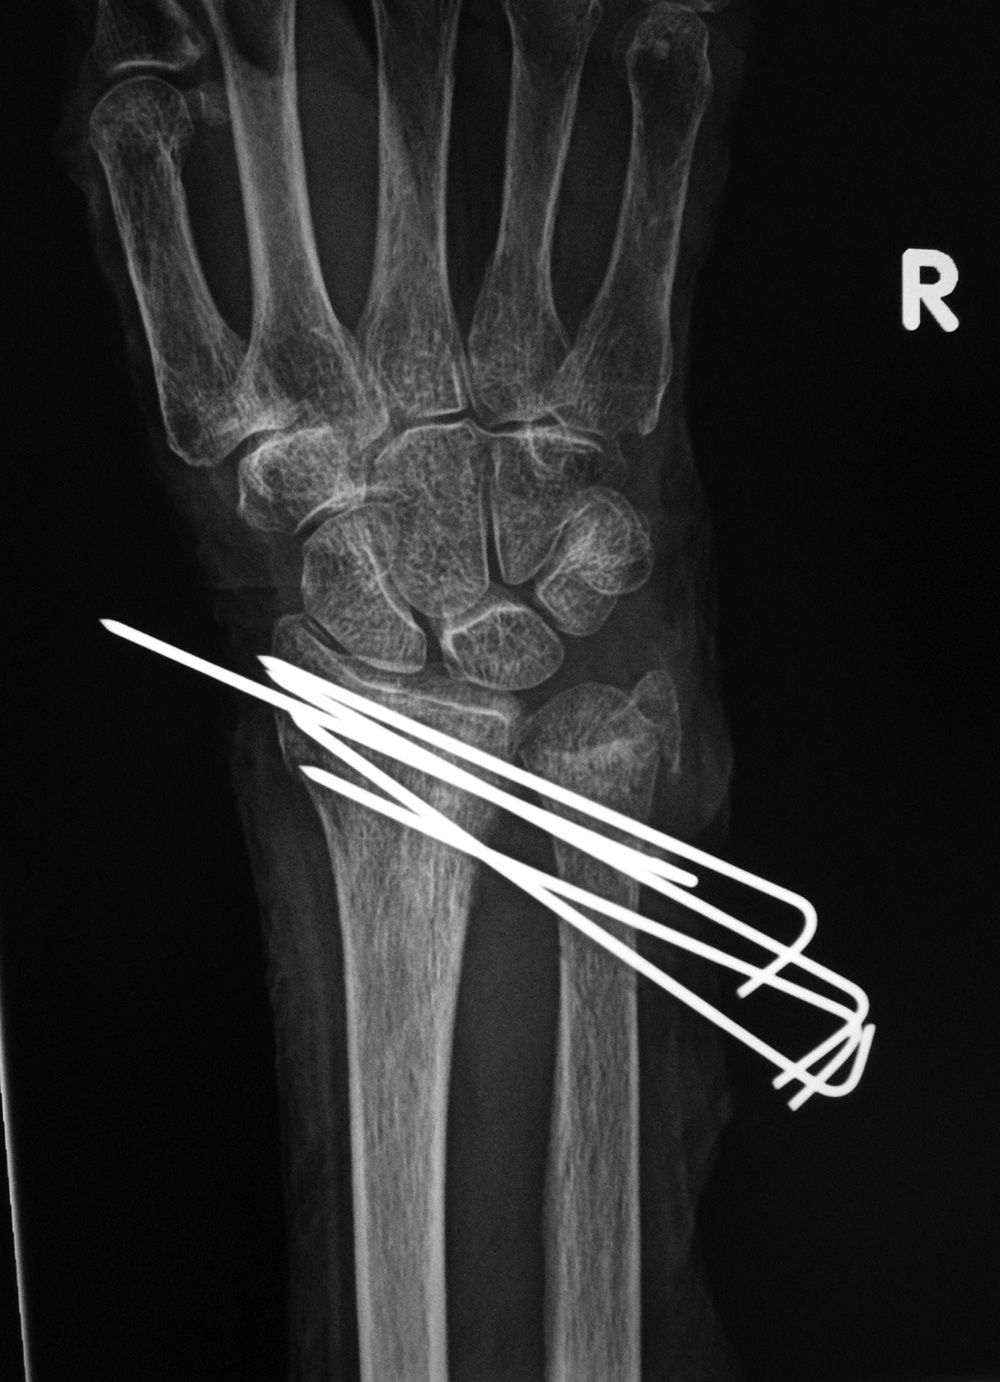

22 year-old man with syndesmotic screw placement for medial avulsive ankle injury. The screws fractured and loosened and were later removed. |